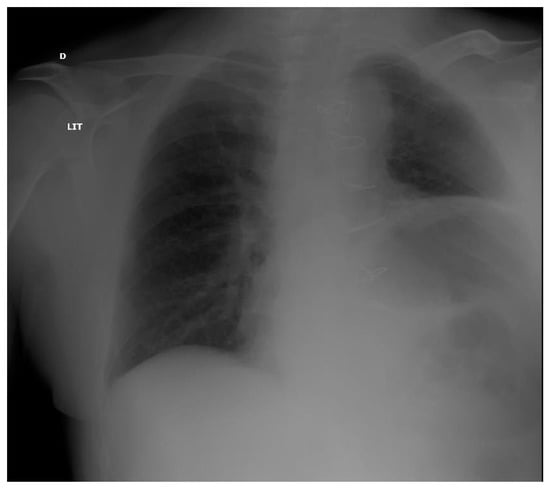

| Yamazaki [47] | CABG (200) | Incidence and factors associated with hemidiaphragm elevation after CABG | radiological study | 14.5% hemi-diaphragm elevation after CABG | Diabetes and use of internal thoracic artery grafting are risk factors | |

| DeVita [51] | Cardiac surgery (92) | Incidence of phrenic neuropathy after cardiac surgery | radiological and EPS studies | Abnormal DM in 54% of patients with abnormal CR 57% PNI among patients with abnormal DM | ||